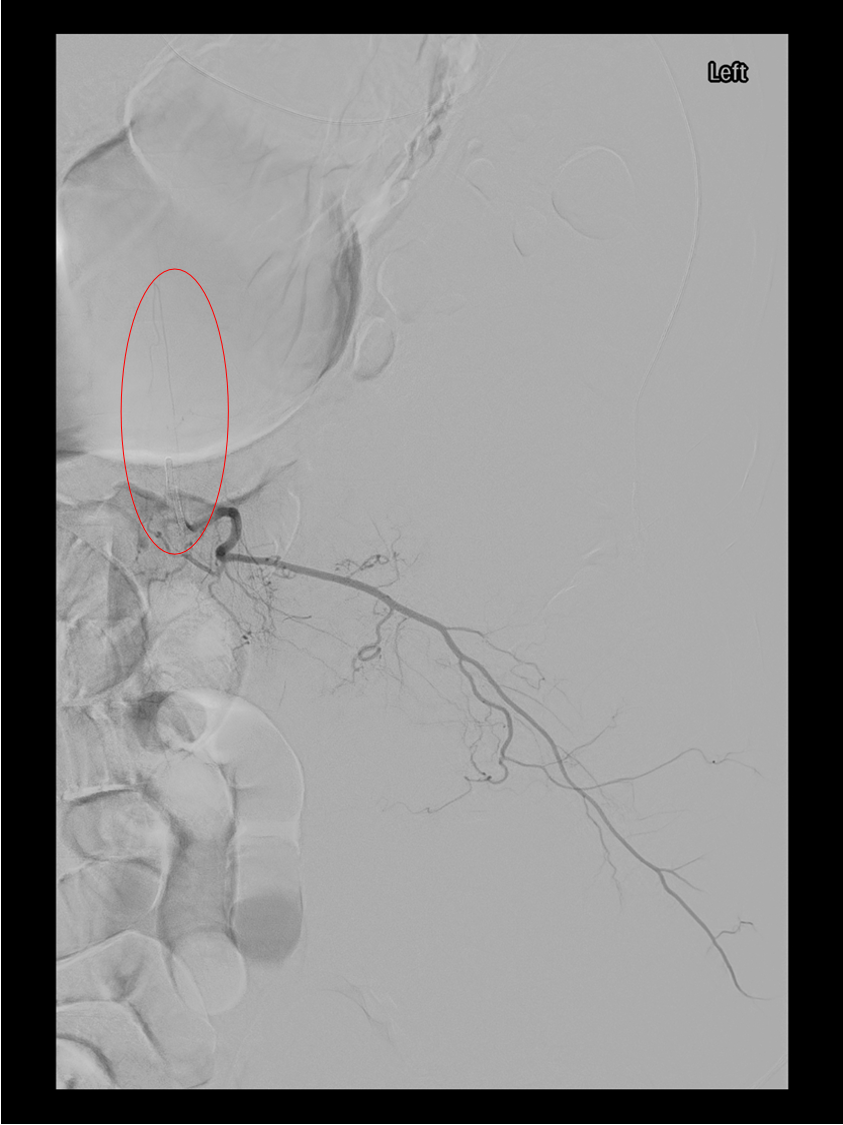

Selective bronchial artery angiogram demonstrating a hypertrophied, tortuous bronchial artery with parenchymal hypervascularity in the territory of disease — the target for particle embolization.